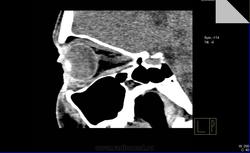

Имеется ли какая-либо орбитальная патология?

Имеется ли какая-либо орбитальная патология?Поделитесь, коллеги,своим мнением,пожалуйста!Если есть,то в глаза патология бросается?

Вот-вот!Меня тоже ничего не смутило.Я и сделал заключение:норма.В направлении ничего толкового написано не было.А почти 2 недели спустя офтальмолог мне с пеной у рта доказывает,что у пациентки отёки необъяснимые в  последнее время,а я(такой-сякой) не вижу утолщения внутренней прямой мышцы глаза!

Я присмотрелся и согласился с ней,извинился,переделал протокол,а про себя поругал за невнимательность.Потом стал присматриваться при других исследованиях(глазниц,головного мозга) к глазницам и почти у всех внутренняя прямая мышца толще и плотнее остальных мышц.

Отсюда вопрос:есть тут или нет эндокринная офтальмопатия?